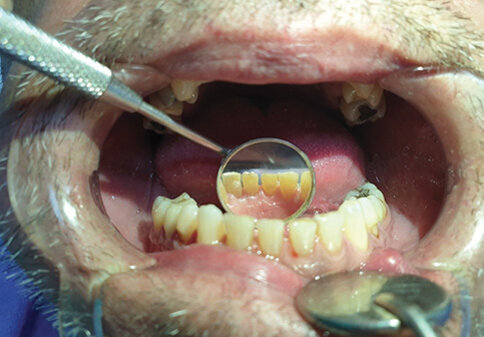

Pacijent A pušač pri prijemu. Jasno se uočavaju naslage u vidu estetski neprihvatljivih pušačkih pigmentacija na svim površinama zuba. Nizak nivo oralne higijene ogleda se u nalazu zubnog kamenca i visokom Plak indexu. Jasno su uočljive pušačke melanoze vidljivog dela desni kao i suvoća i beličaste promene obraznog dela sluzokože. Obložen jezik takođe je karakterističan nalaz višegodišnjeg pušača (Sl. 1.0).

Sl. 1.0: Pacijent A, pušač pri prijemu